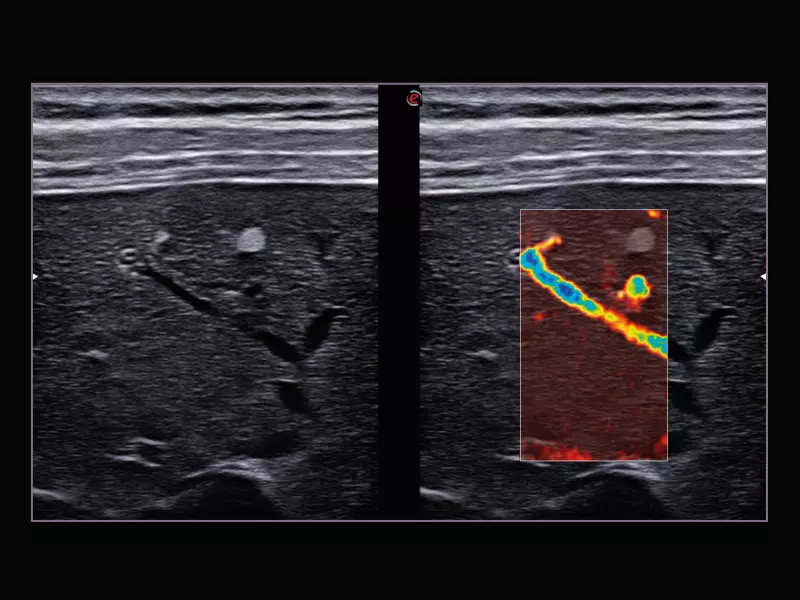

MyLab™9 Platform - XFlow Doppler enhancement in liver vascularization

MyLab™9 Platform - XFlow Doppler enhancement in liver vascularization